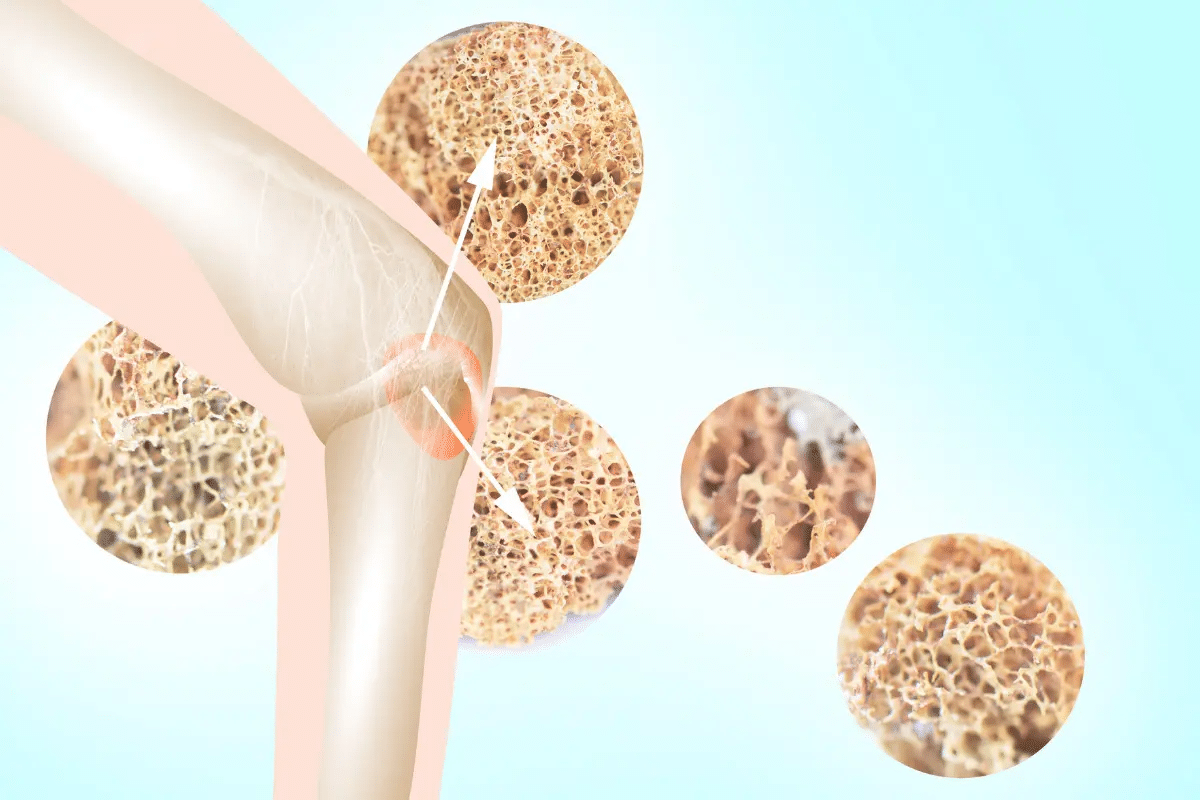

Keeping our bones strong is key, more so as we get older. About 200 million people globally face osteoporosis, a condition that weakens bones, making them prone to fractures. A balanced nutrition plan is vital in stopping bone loss and making bones stronger.Create the perfect osteoporosis diet. This essential guide lists the 15 best foods to boost bone density and prevent fractures naturally.

Osteoporosis is a silent epidemic that affects millions worldwide. It’s a major health concern that we need to focus on. We reach our peak bone mass around age 30. After that, keeping our bones healthy is key.

Osteoporosis is a big health problem globally. It affects about 200 million people. The condition makes bones weaker and more prone to fractures.

How Bone Density Changes Throughout Life

Bone density changes as we age. We usually reach our peak bone mass in our early thirties. Exercise and physical activity are key for healthy bones from childhood to adulthood.

The Bone Remodeling Process

Bone remodeling is a never-ending cycle. It breaks down old bone and makes new one. Nutrients like calcium and vitamin D are essential for this process. They help control bone cells.

This process involves two main cells: osteoclasts and osteoblasts. Osteoclasts break down bone, while osteoblasts build it. A balance between these cells is vital for strong bones.